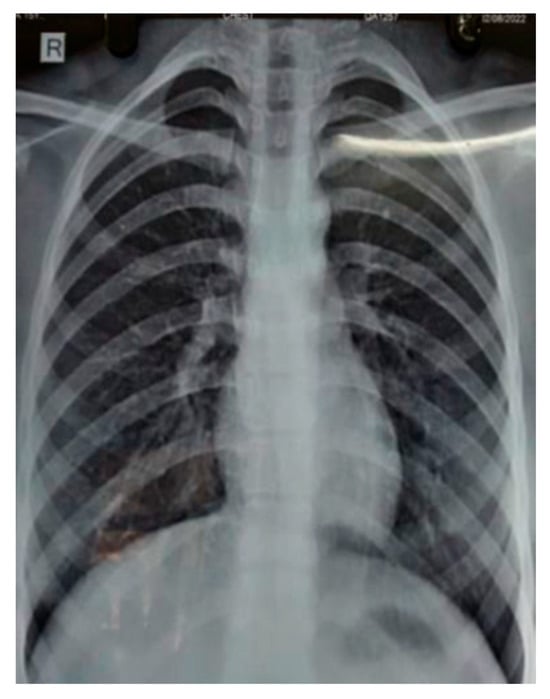

A chest radiograph showed patchy consolidation in the right lower lobe and mild pleural effusion. To obtain a better view of the lesion, a high-resolution computed tomography scan was performed, which showed patchy foci of air space consolidation in the right lower lobe along with pleural effusion (Figure 1).

The patient developed a dry cough after receiving her fourth cycle of chemotherapy and was hence referred to our side for the same. Since none of the routine investigations were successful in identifying a cause for the condition, specific tests like mycoplasma pneumoniae antibodies, rheumatic factor, and antinuclear antibody tests were conducted, and the results were negative. A repeat chest radiograph revealed non-segmental patchy air space consolidation areas in the right lung’s lower zone. The high-resolution computed tomography scan of the thorax also revealed similar findings like areas of “ground glass” opacities at the base of the right lung, with patchy foci of air space consolidation, mostly in the subpleural region (Figure 1). Due to inconclusive evidence from blood and radiological investigations, a decision was made to subject the patient to bronchoscopy.

A subsequent chest X-ray suggested that the lesions had disappeared entirely (Figure 2). This further confirmed that the patient’s condition was caused by reaction of the body towards trastuzumab, and it should be noted as one of the side effects of the drug.

Figure 2. Chest radiology of 58-year-old female showing resolution of right lower lobe consolidation after stopping trastuzumab therapy.